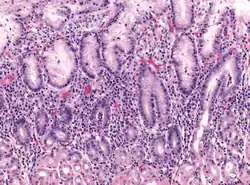

Micrograph showing gastritis. H&E stain. | |